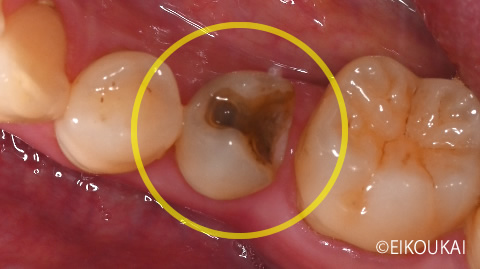

治療内容 左下5番に虫歯があり、虫歯除去から根の治療、被せ物をつけるところまで治療をしました。

被せ物は見た目が綺麗で今後虫歯になりにくいセラミッククラウンで行いました。金額 左下5 セラミッククラウン 118,800円 治療期間 1ヶ月 通院回数 6回 リスク/副作用 強い噛み合わせ、強い噛み締め食いしばりで欠けるリスクあり。